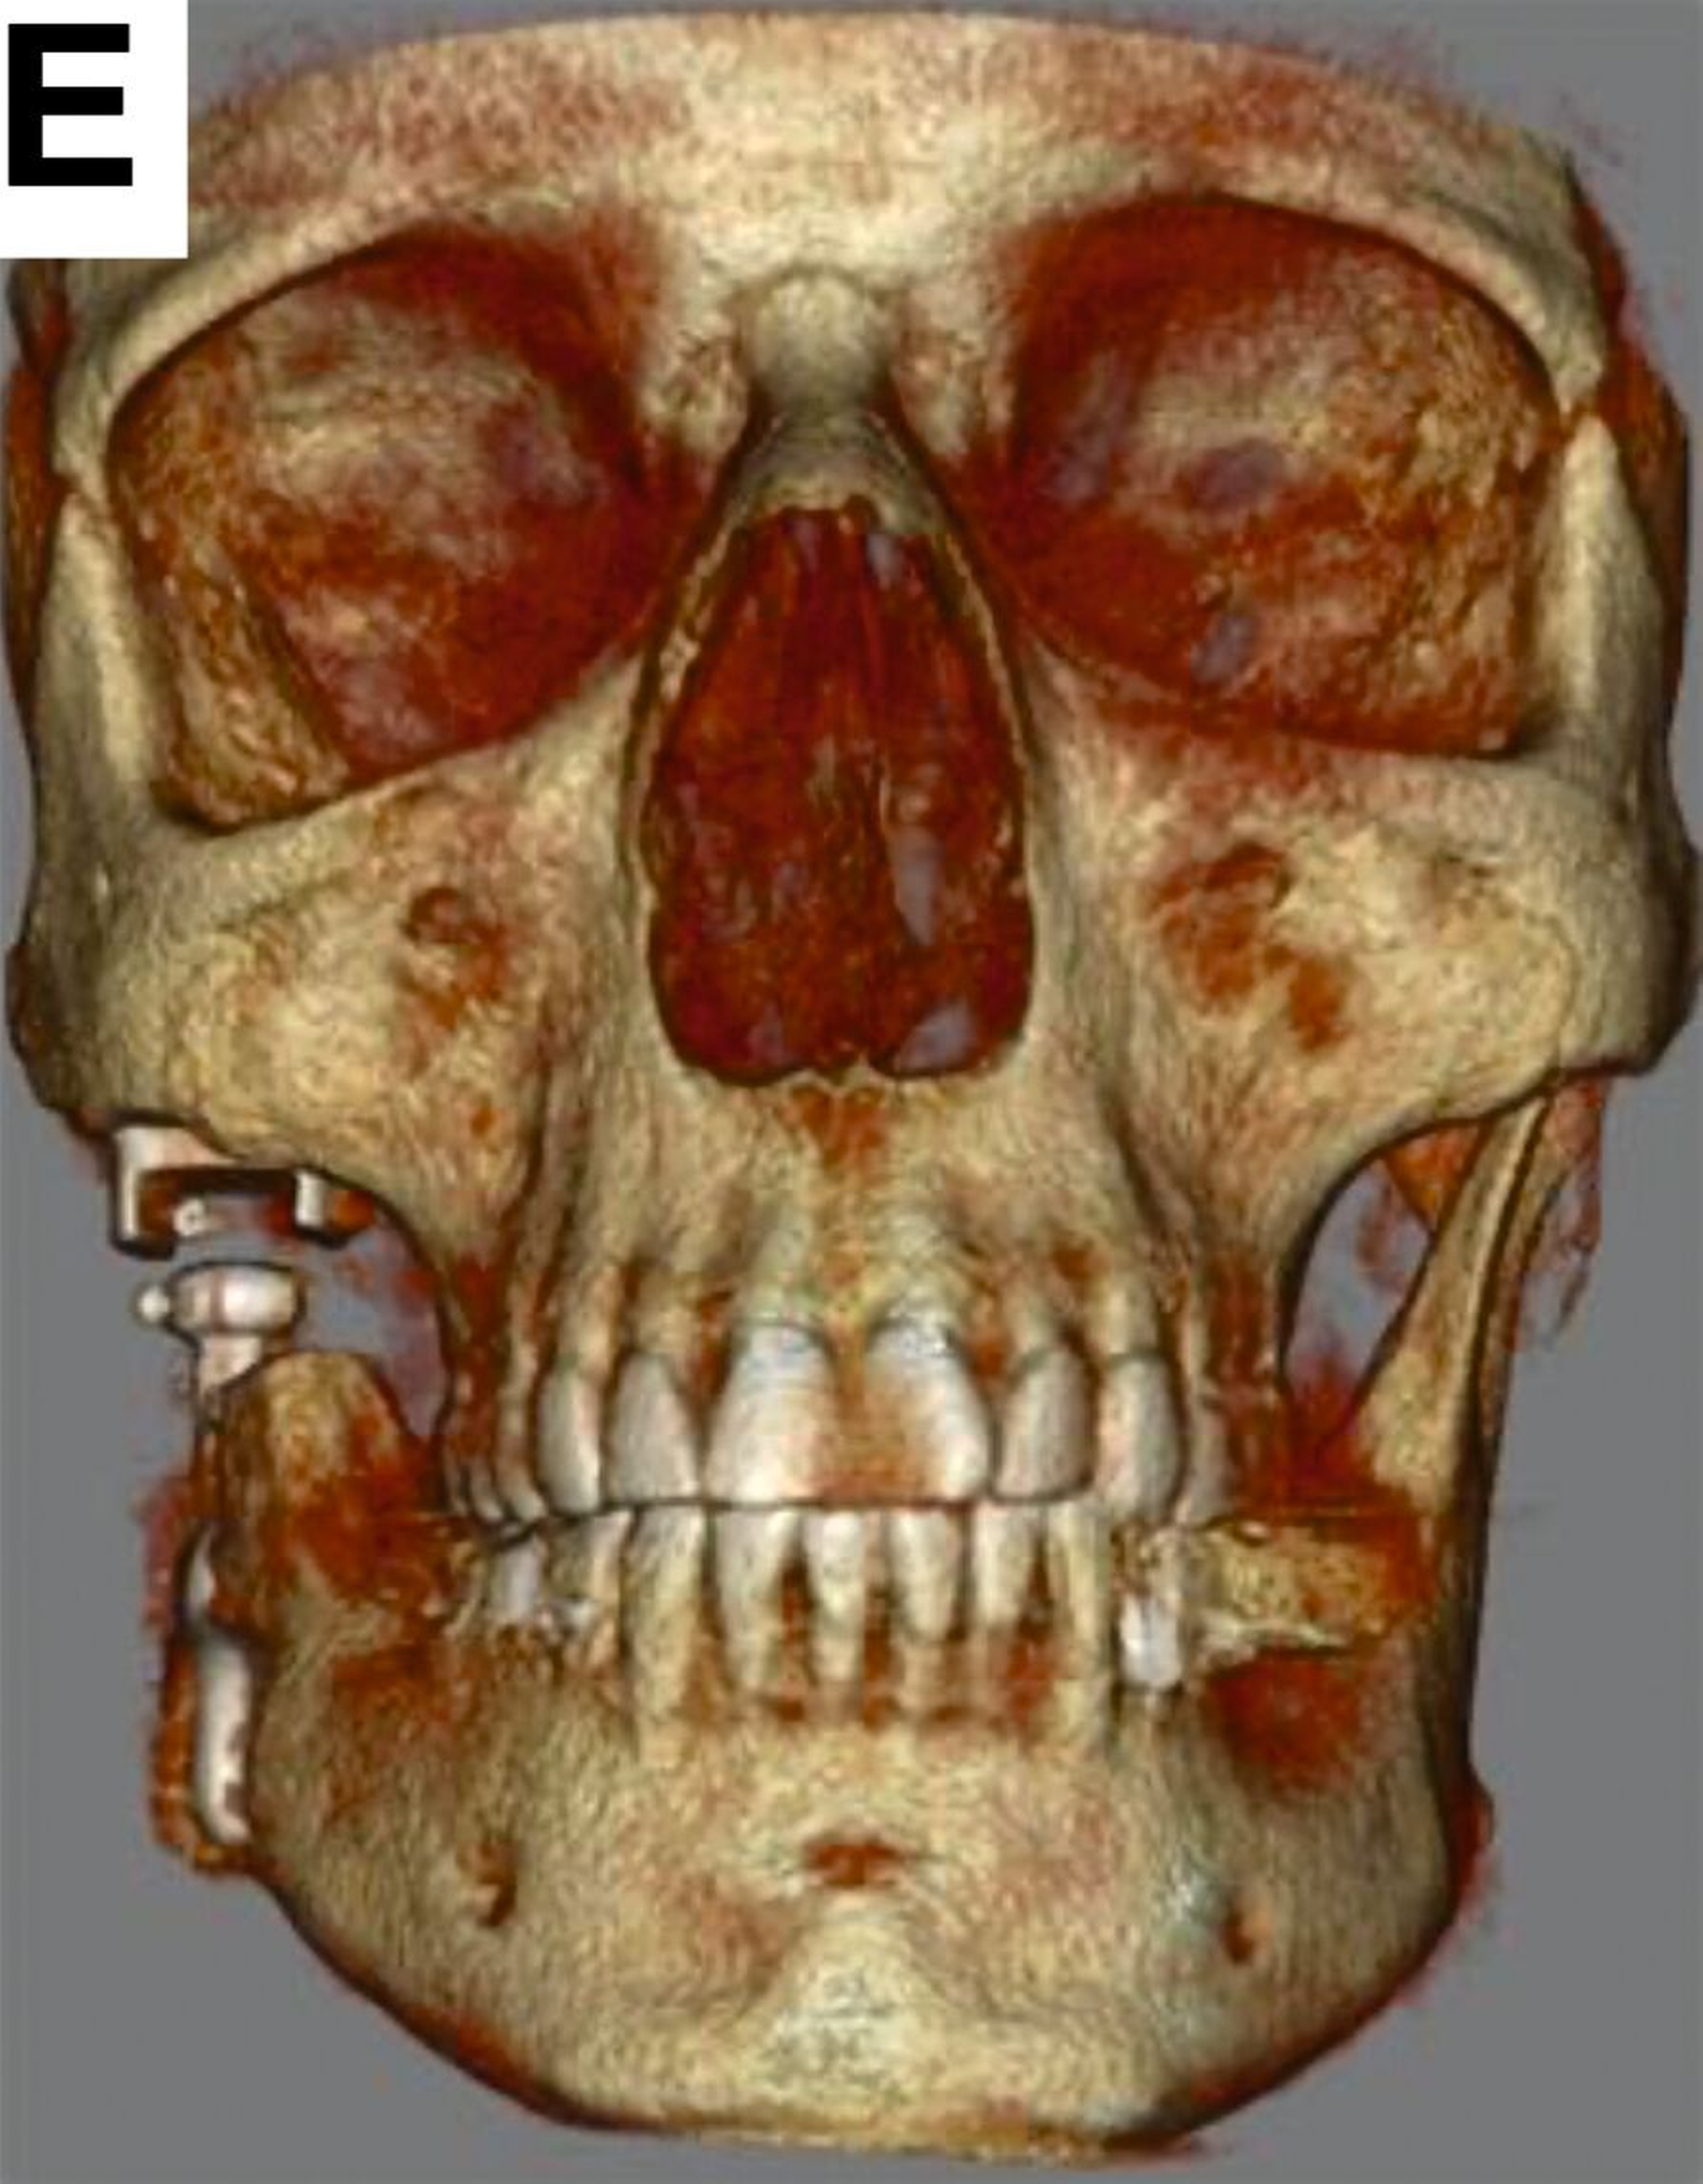

Die finale patientenspezifische CAD/CAM-Kiefergelenkendoprothese wurde von der Firma Materialise in Löwen, Belgien, hergestellt. Vier Monate nach der Explantation konnte die Patientin erfolgreich mit Ersatz von Kondylus und Fossa mandibularis versorgt werden (Abbildung 4).

Der postoperative Verlauf verlief unauffällig, so dass bereits nach vier Wochen mit leicht dehnenden Mundöffnungsübungen begonnen werden konnte (Abbildung 5).